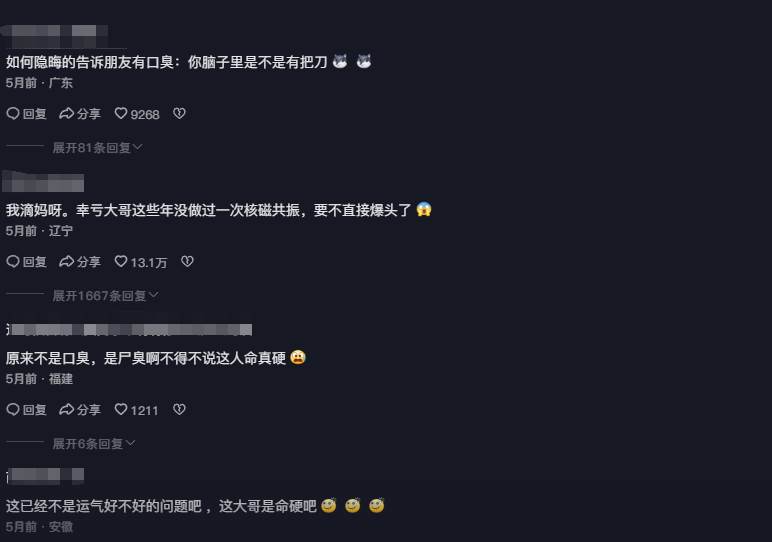

口腔科主任檢查時,觸摸到阿福頭部有異物,建議他做進一步X光檢查。結果讓醫生大驚失色——阿福的腦袋里竟藏著一把長達十公分的雙刃刀!這把刀尖端嵌在顱骨中,由于空氣接觸,刀身已經嚴重銹蝕。更令人不可思議的是,這把刀在阿福的腦袋里「安家」了四年,而他竟毫不知情!

醫生解釋,刀的位置極其刁鉆,幸運地避開了大動脈、氣管和食管,才讓阿福奇跡般活到了今天。然而,醫生同時警告,隨著吞咽動作,刀的移動可能隨時威脅他的生命。一旦刀割破大動脈,后果不堪設想。

手術后,醫生解釋,阿福之所以能活下來,與他頻繁輸液和服用消炎藥有關,意外抑制了感染擴散。這讓人不禁感嘆生命的頑強與奇跡的發生。然而,這把刀是如何[插·入]阿福腦袋的謎團仍未解開。